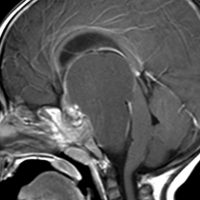

成人の第3脳室内部に局在する頭蓋咽頭腫です。経脳梁法で両側のモンロー孔から全摘出しました。下垂体組織は残っています。これは乳頭状頭蓋咽頭腫と呼ばれるもので,成人にしか発生しません,のう胞がなく石灰化もないのが大きな特徴です。境界が明瞭で柔らかく摘出が簡単なタイプとして知られています。この患者さんも術後に下垂体機能不全も視床下部障害も生じませんでした。